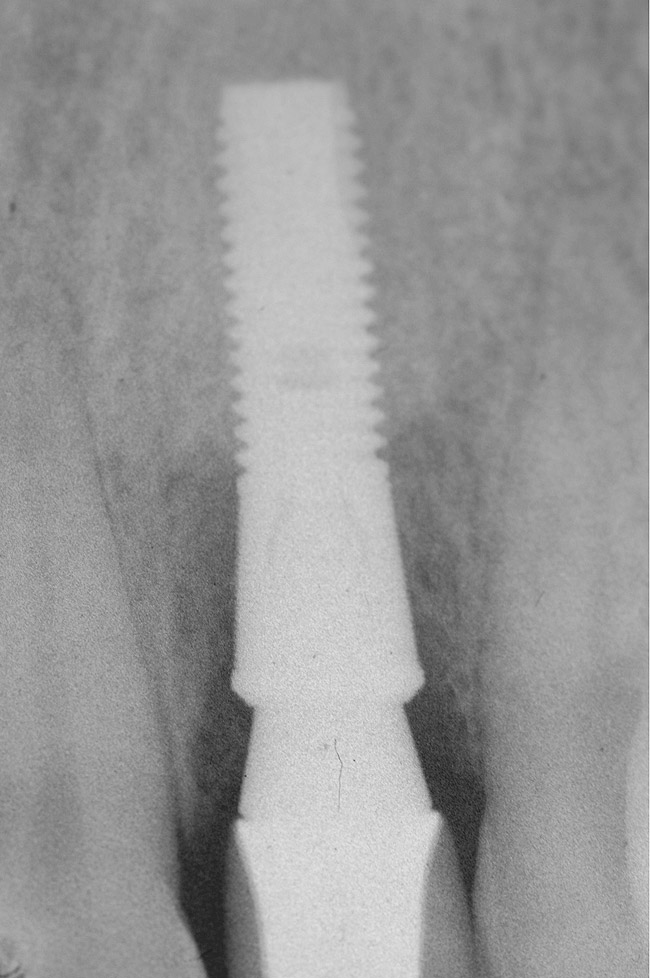

Figure 9  Extraction of teeth Nos. 29 and 31 with immediate implants (Straumann USA, Waltham, MA) placed into the site.

Figure 9